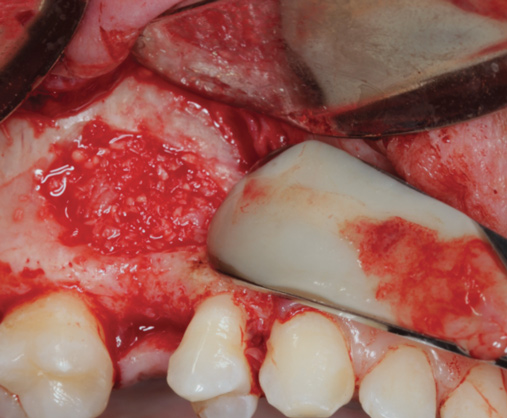

Fig 3. PRF fragments are then added to a bone grafting material and mixed with PRF exudate to produce a sticky, consistent bone grafting material.

Figure 3

Fig 5. Bone grafting material combined with PRF fragments to fill a medium-sized sinus.

Figure 5

Fig 6. The packing of bone grafting material is made more convenient with improved handling due to the overall change in bone graft consistency when combined with PRF.

FIgure 6

The biological advantages of using PRF for sinus augmentation procedures have been well-documented.14 PRF serves as a scaffold capable of protecting the Schneiderian membrane, may be combined with bone grafting materials to improve their handling and stability, and has been shown to increase new blood flow to the poorly vascularized area of the sinus cavity (Figure 1 through Figure 3). As a result, PRF is commonly used for all sinus augmentation procedures. The size of the sinus cavity has been the primary deciding factor for when to use PRF alone versus combined with a bone grafting material.

One reported limitation of using PRF alone for sinus augmentation procedures is its use in wide sinuses. Avila et al demonstrated that lateral sinus augmentation procedures performed with an allograft in narrow sinuses (<10 mm) and medium sinuses (10 mm to 15 mm) demonstrated roughly three times more vital bone after a 6-month healing period when compared with wide sinuses (>15 mm) (Figure 4).24 In response to these findings and the clinical experiences of numerous oral surgeons using PRF alone for sinus augmentation procedures, it has been recommended that sinuses >15 mm be regenerated in a combination approach with a bone grafting material. Therefore, all sinuses greater than 15 mm should be regenerated using PRF cut into small fragments with a bone grafting material (Figure 5 and Figure 6).